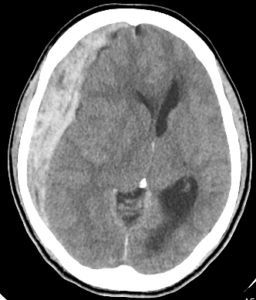

경막하 출혈의 진단은 환자의 신체검사와 함께 여러 가지 검사방법을 통해 이루어집니다.

- CT 또는 MRI 스캔 : 출혈량과 위치를 확인하기 위해 실시됩니다.